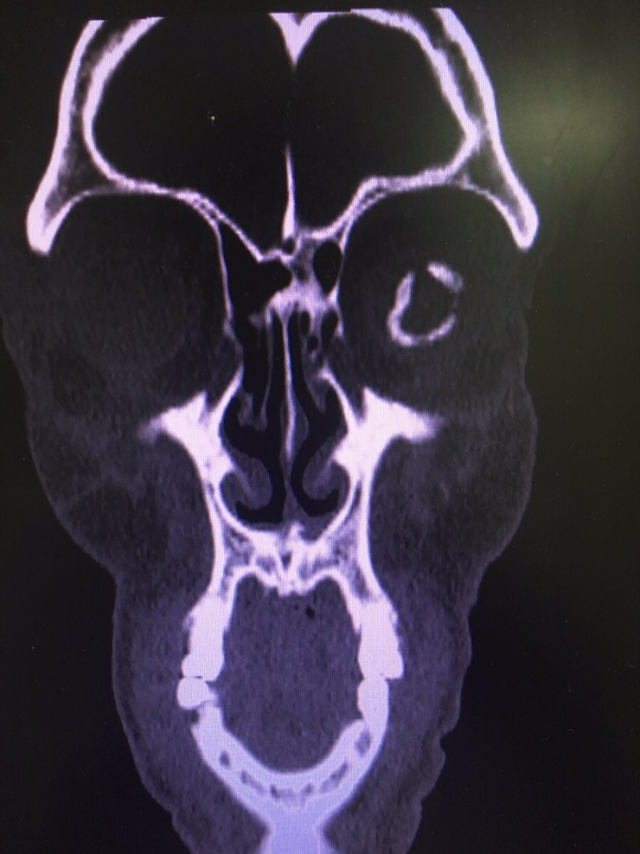

열상 환자의 facial bone CT를 열었다. 골절 여부 체크하려고 살폈는데, 좌측 안구에서 동그란 석회물질이 포착됐다.

"눈에 반지가 있으시네요."